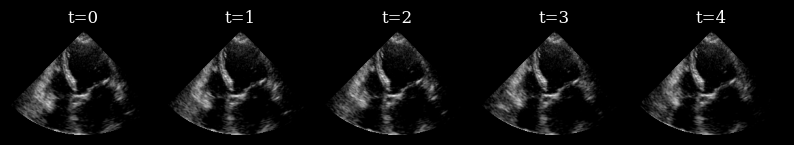

Here we load a sequence of ultrasound frames from the CAMUS validation set. This will be our ‘ground truth’ target sequence, that the agent will need to reconstruct from a small budget of focused scan lines

[7]:

n_frames_to_plot = 5

fig, _ = plot_image_grid(

data_sc[:n_frames_to_plot],

titles=[f"t={t}" for t in range(n_frames_to_plot)],

ncols=n_frames_to_plot,

remove_axis=True,

vmin=-1,

vmax=1,

)